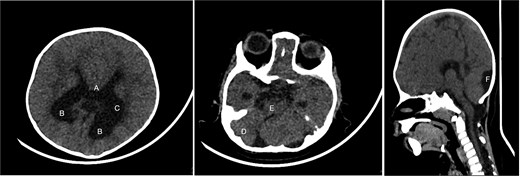

An 11-month-old female infant, born to unrelated Saudi parents, was referred to our facility with unilateral left coronal craniosynostosis, congenital microcephaly, global developmental delay, and a confirmed ZIC1 gene mutation. Comorbidities included a patent foramen ovale, aortopulmonary collateral vessel, G6PD deficiency, and gastroesophageal reflux disease (GERD). At birth head circumference was 29 cm (<first percentile), and progressive skull asymmetry and squinting were noted over time. Developmentally, she exhibited delayed gross and fine motor skills with limited object transfer. On examination, she was alert and visually tracking, with inward ocular deviation (esotropia). Head circumference was 37 cm (<first percentile) with anterior plagiocephaly and towering of the left frontal region (Fig. 1). Pupils were equal and reactive. Fundoscopy and cranial nerve examinations were unremarkable. Gross motor power was within normal limits, except for moderate lower limb spasticity. 3D reconstruction computed tomography (CT) confirmed premature fusion of the left coronal suture with subtle elevation of the superolateral orbital rim, indicating harlequin sign (Fig. 1). Brain CT showed corpus callosum agenesis, colpocephaly, mild ventriculomegaly, right cerebellar and pontine hypoplasia, and a large cisterna magna, consistent with the reported ZIC1-related malformation spectrum (Fig. 2). Given the progressive deformity and concerns of increased intracranial pressure that might be partially contributing to her neurodevelopmental delay, anterior cranial vault expansion with fronto-orbital advancement was performed jointly by the neurosurgery and plastic craniofacial teams (Fig. 3). Intraoperatively, left-sided dural tension was appreciated, indicating localized increased intracranial pressure. The orbital bandeau was reshaped and advanced, achieving immediate cosmetic improvement (Fig. 4). The patient tolerated the surgery well and recovered uneventfully. At her 4-month follow-up, she showed developmental progress including standing without support, purposeful hand use, and verbalization (“Baba”). At 6-month follow-up, brain CT revealed areas of bone resorption which led to the placement of a ventriculo-peritoneal shunt (Fig. 5). The known association of ZIC1 mutation with tethering of the cord prompted spinal magnetic resonance imaging (MRI) screening. Positive findings indicated an untethering procedure, which was successfully done (Fig. 6).

Intra-operative gross appearance of the left unilateral plagiocephaly with towering.